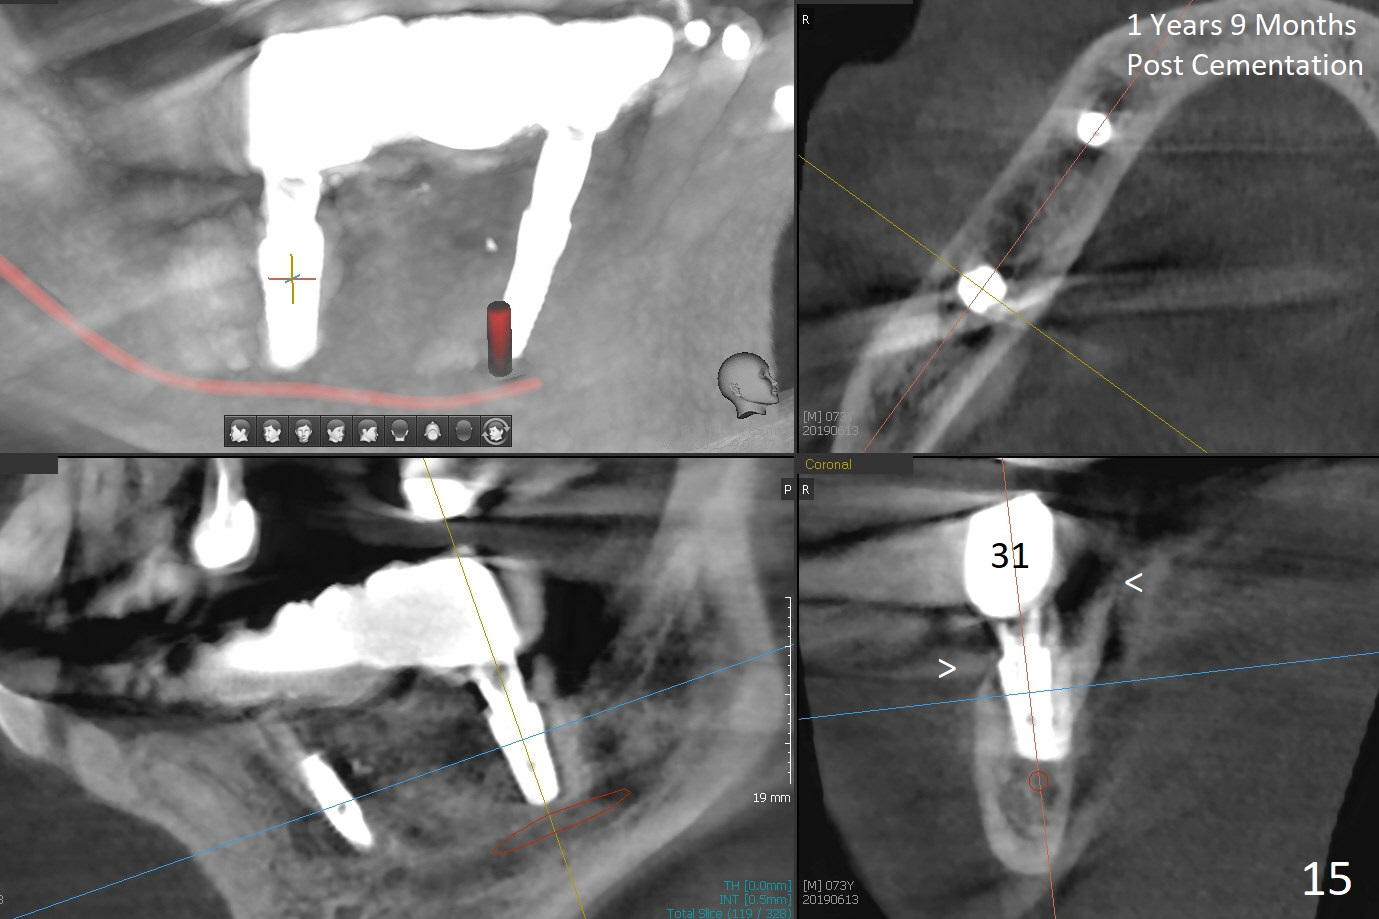

The patient will return in two weeks (total 2 months postop). The abutment at #29 will be changed to a longer one (3.9x7(6) mm). Provisional FPD will be fabricated with an emphasis to push the surrounding (especially lingual) gingiva away from the abutments, most likely using gauze as gingival retraction cord. The crown at #2 will be trimmed to have clearance. Fig.13 is taken 3 months post cementation. CBCT taken 1 year 9 months post cementation shows the uneven buccal (B) and lingual crests (Fig.14,15 arrowheads).